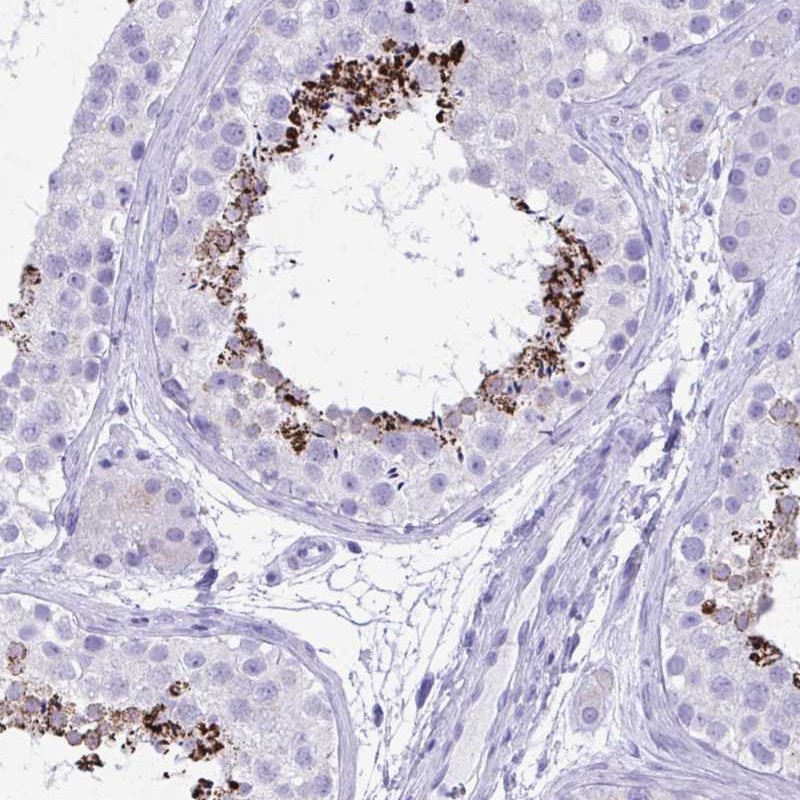

Immunohistochemical staining of human testis shows strong cytoplasmic positivity in cells in seminiferus ducts.